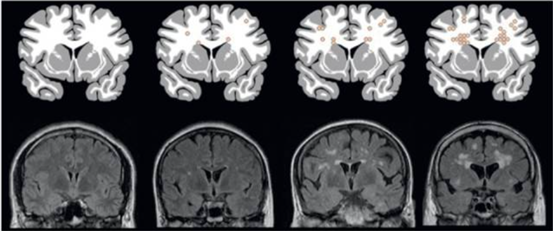

脑缺血灶严格来讲并不属于临床诊断,不是一个疾病名称,而是一个影像学术语或者说是核磁检查对一种病理改变的描述,它可以表示一种缺血缺氧的状态。一般是指在头颅磁共振上见到的斑点或斑片状T2WI/FLair异常高信号。其专业名称为假定血管起源的脑白质高信号(WMH),属于脑小血管病的范畴。

评估方法主要有两种:改良Fazekas法(3级)、人工智能计算脑白质高信号体积